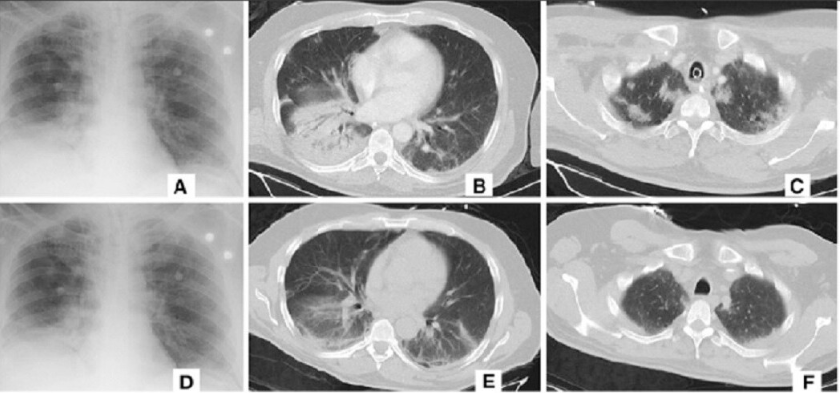

알리바바, CT 영상으로 코로나 19 진단하는 AI 진단 시스템 현장 투입

- 진단 시간 20초, 96%의 정확도

- 목표는 코로나에 걸린 폐 CT와 일반 폐렴 이미지를 분류하는 것

- 중국 전역의 코로나 확진 자의 폐 CT 이미지 및 데이터 5000여 건을 수집하여 학습함

- 일주일간 30,000건의 폐렴 사례를 지원했고, 현재 중국 후베이, 상해, 광동 등 16개 지역의 26개 병원에 적용 중

중국에서는 코로나 확진에 CT의 임상 진단 결과를 활용하고 있다. 그런데 한 명의 폐렴 환자를 진단하기 위해서는 약 300장의 CT 이미지를 확인해야 하고, 이 과정에 15분가량의 시간이 걸려 의료진의 업무 부담이 큰 상황이다. 높은 정확도로 폐렴을 분류할 수 있는 AI 기술로 진단에 투입되는 시간과 비용이 크게 경감될 것으로 기대된다.

이투 헬스케어, 코로나 19 용 AI 흉부 스캐너 분석 시스템 현장 투입

- 코로나19 사례를 추적하고 분석할 수 있는 시스템

- 병변이 발견된 영역을 자동 감지(detection) 2~3초 내에 정량적인 분석을 시행함

- 이를 통해 폐 CT 이미지에 대한 분석을 실행하고, 바이러스로 손상된 폐에 대한 치료를 결정하도록 도움

- 현재 상하이 공중보건 클리닉센터에서 코로나 19 진단용 흉부 CT 지능화 평가 시스템을 지원하고 있음